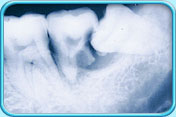

Since it is difficult to clean the surfaces between the impacted tooth and the adjacent tooth in front, dental plaque will accumulate there and cause tooth decay on these tooth surfaces.

The inflammation of the surrounding tissues caused by the dental plaque, together with the pressure of the wisdom tooth pushing on the adjacent tooth in front, may cause the root of the adjacent tooth to resorb.